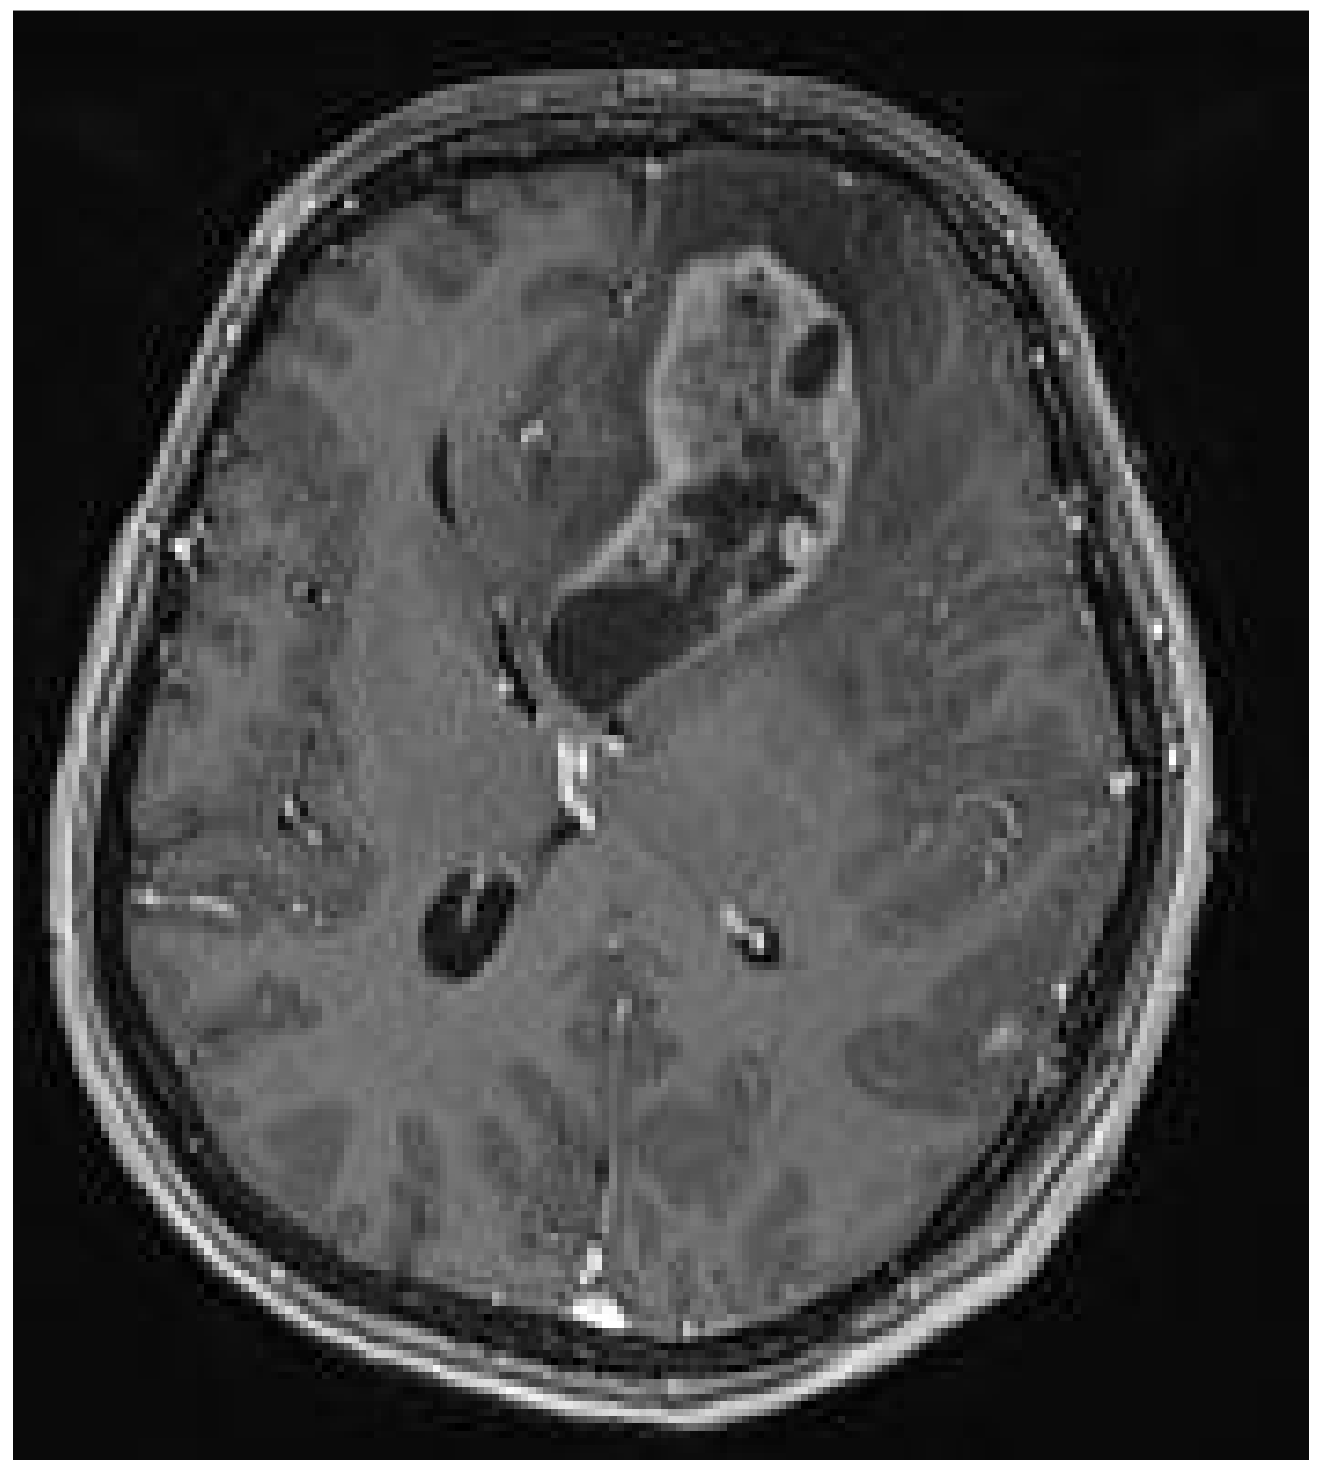

2. Case Presentation